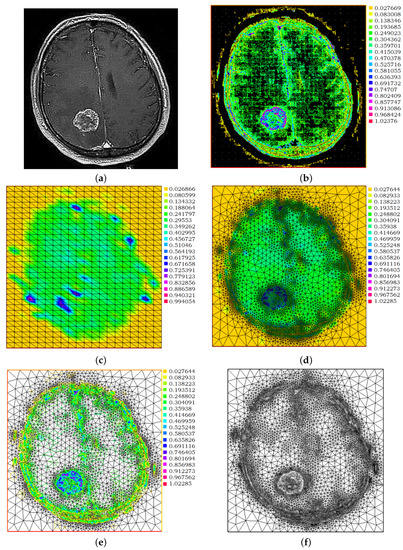

A Metastatic Brain Tumor Example

3. Experimental Results